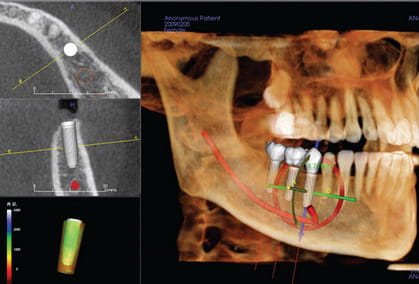

۳. برنامه ریزی دقیق جراحی

تصاویر سه بعدی CBCT امکان شبیه سازی دقیق محل کاشت ایمپلنت را فراهم می کنند. با استفاده از این تصاویر، دندانپزشک می تواند:

- زاویه ورود ایمپلنت را مشخص کند.

- بهترین عمق و موقعیت را برای ایمپلنت تعیین کند.

- از ایجاد فشار و آسیب به استخوان جلوگیری نماید.

این امر باعث کاهش عوارض بعد از جراحی و افزایش موفقیت ایمپلنت می شود.